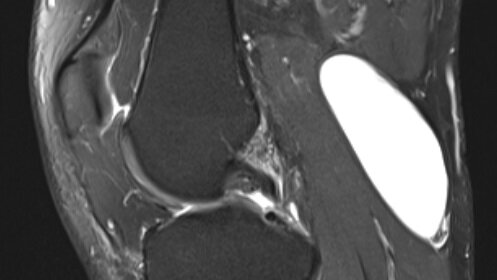

Киста Бейкера, также известная как подколенная киста или синовиальная киста. Довольно частая находка в области коленного сустава. Представляет собой заполненную жидкостью полость, которая образуется в задней части колена – подколенной ямке. Киста Бейкера названа в честь британского хирурга Уильяма Бейкера, впервые описавшего ее в 19 веке. Секрет. Самое большое заблуждение пациентов, многих врачей, да и самого доктора Бейкера (но ему простительно, он жил в 19 веке), в том, что это НЕ киста, а одна из синовиальных сумок коленного сустава, которая в норме находиться в спавшемся состоянии...

Кистой Бейкера (иначе — подколенной кистой) называют появляющееся в подколенной ямке образование, заполненное жидкостью. Она часто мешает двигать ногой и вызывает неприятные ощущения. Киста Бейкера встречается и у взрослых, и у маленьких пациентов. Узнайте, как вовремя распознать и вылечить эту болезнь. Время прочтения: 4 минуты Коленный сустав — это сложное образование, включающее четыре кости, множество связок и сухожилий. Он покрыт суставной капсулой снаружи, а внутри содержит жидкость, облегчающую движения костей...